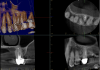

Figure 7 shows another tooth that was diagnosed with a necrotic pulp; Figure 8 shows a preoperative CBCT slice from the volumetric scan of the tooth. The clinician observed that there was more than one canal in the mesiobuccal system and that a periapical lesion was present. Lesions were visible radiographically on every root, adjacent to numerous portals of exit in the apical one-third. In this case, the clinician aimed to be more conservative and was able to better maintain the original anatomy. In the mesiobuccal root, the canals crisscrossed, and considering the delicate anatomy in the apical one-third, it was imperative to keep the foramen as small as practical. A much larger palatal canal was also observed. The clinician provided a coronal seal buildup before the rubber dam was removed from the tooth. Figure 9 shows the postoperative 2D radiograph.

Fig 7. Preoperative radiographic image (Fig 7), preoperative CBCT (Fig 8), and postoperative radiographic image (Fig 9).

Figure 7

Fig 8. Preoperative radiographic image (Fig 7), preoperative CBCT (Fig 8), and postoperative radiographic image (Fig 9).

Figure 8

Fig 9. Preoperative radiographic image (Fig 7), preoperative CBCT (Fig 8), and postoperative radiographic image (Fig 9).

Figure 9